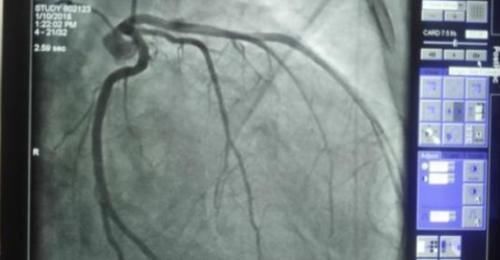

在达芬奇流传后世的众多手稿中,有学者注意到了一幅绘制心脏结构的解剖图,图中还明显地将心肌小梁给画了出来。前段时间欧洲分子生物学实验室在《自然》期刊上发表了一篇关于心脏结构最新认知的论文,研究人员通过研究和分析2.5万张磁共振的心脏图像,发现心肌小梁或许还有更多功能。

简而言之,心肌小梁这个机构在以往的医学研究中并未得到重视,因此它的潜在功能也一直未被发现。直到欧洲分子生物学实验室的研究人员对来自英国生物样本库的2.5万张心脏磁共振图像进行研究,才进一步认识了心肌小梁的生理作用。研究人员发现,心肌小梁的存在使得血液在流动的时候受到更多的阻力。